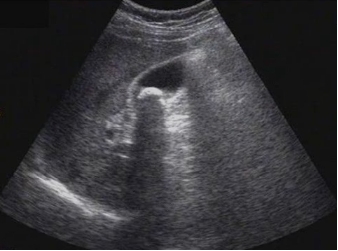

試題3:患者女性,50歲,間斷上腹隱痛半年,診斷為(2分)

【答案】C